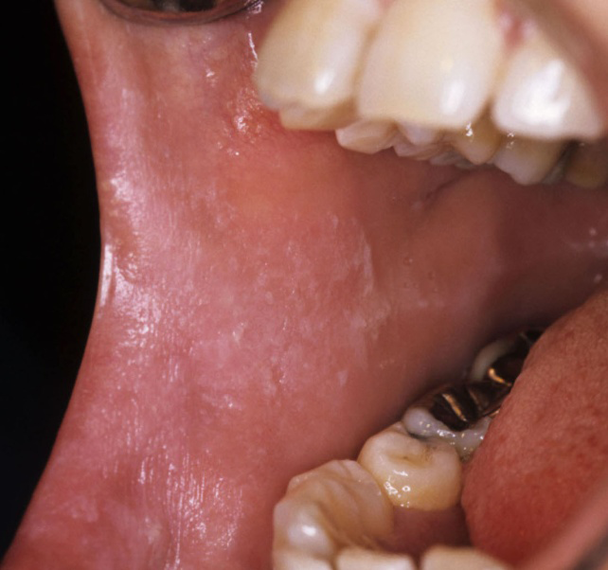

口腔扁平苔癬(斑状型)

口角から頬粘膜にみられた斑状型扁平苔癬